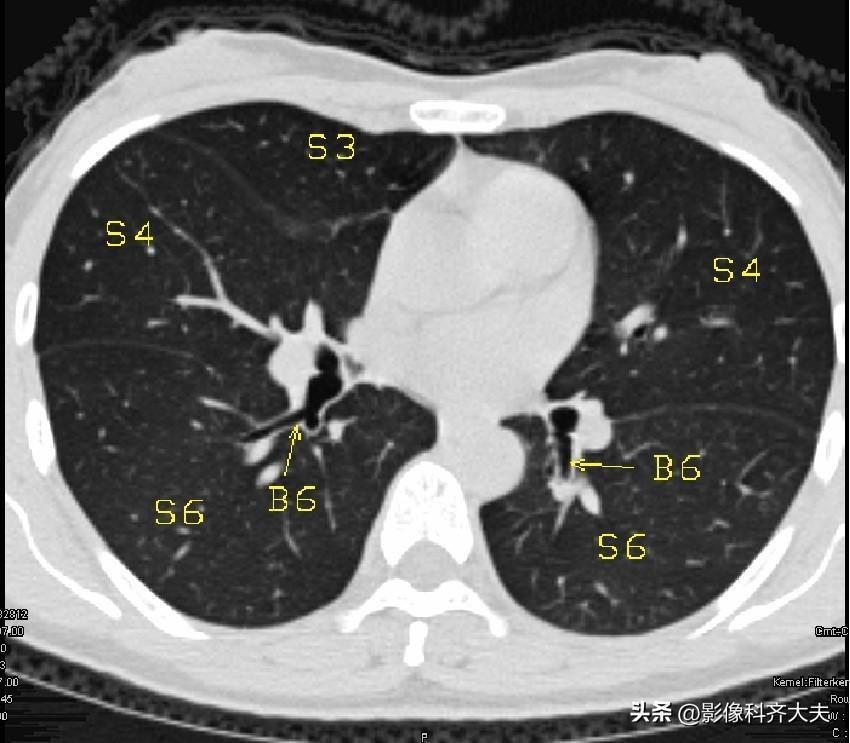

图13

图14

▲B5:右中叶内侧段/左舌下段支气管,BS:基底干支气管,MLB:中叶支气管,S5:右中叶内侧段/左舌下段